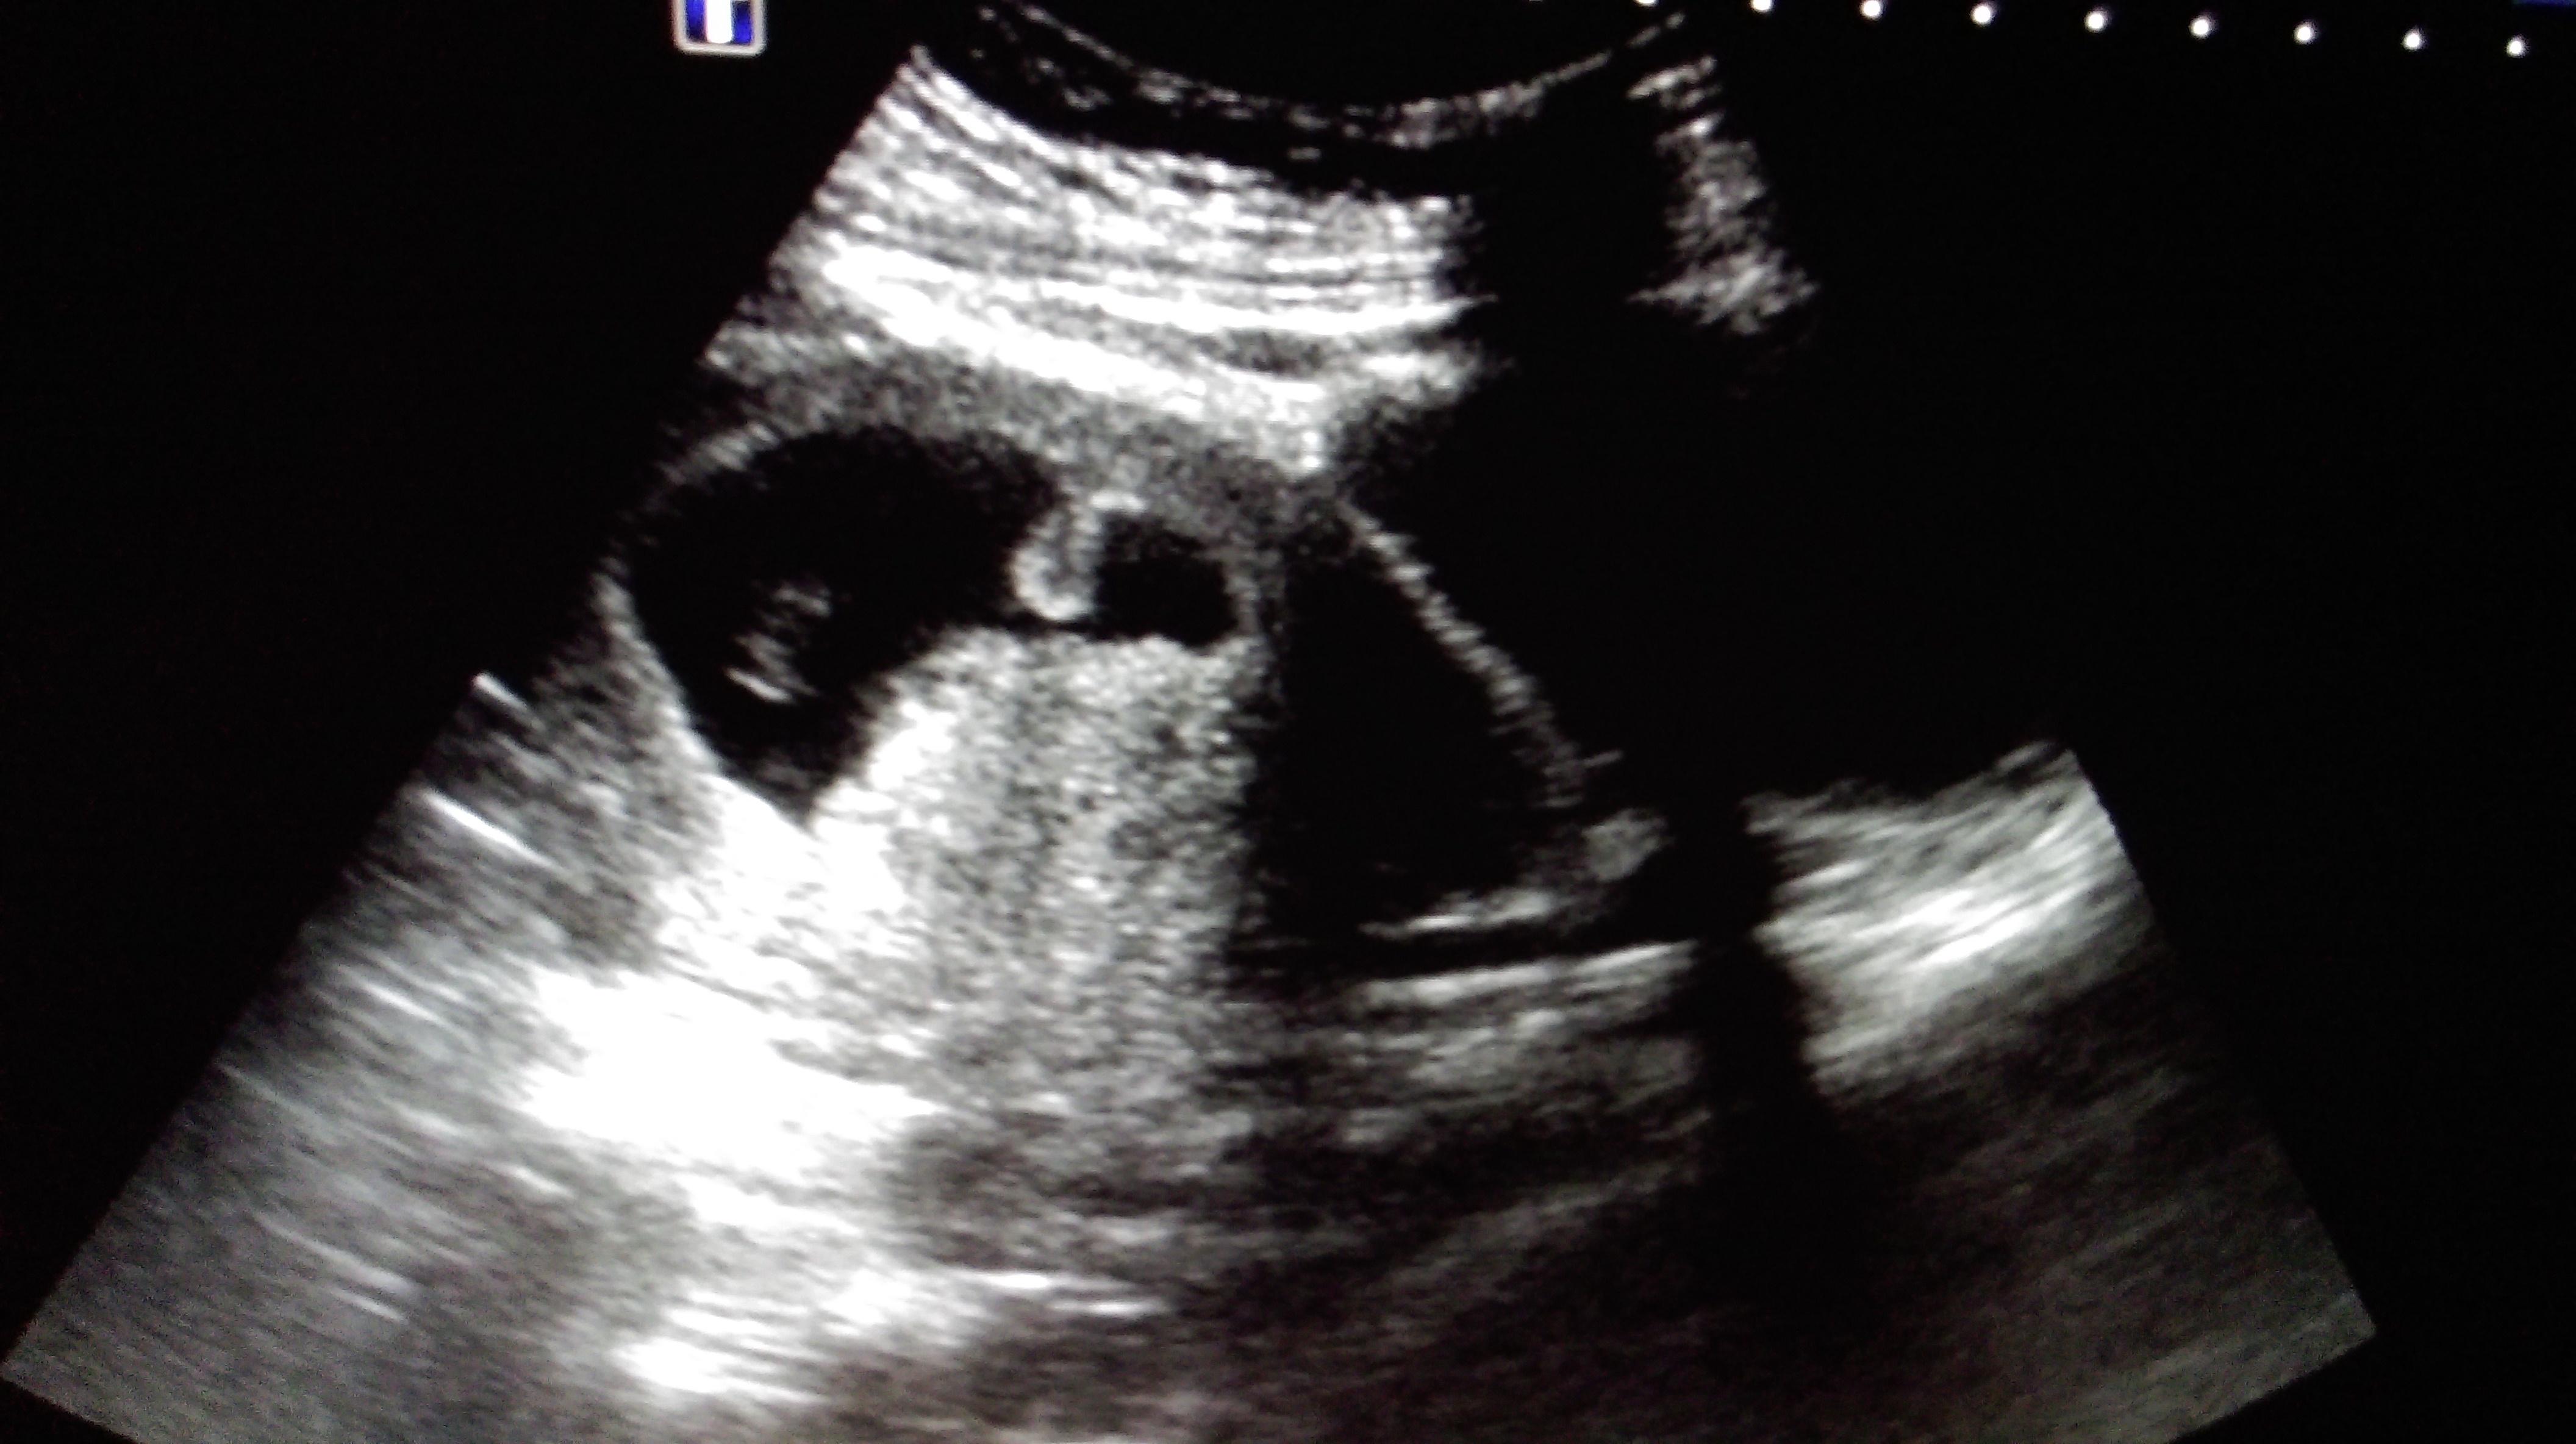

早孕9周妊娠囊这个形态怎么报?

妊娠囊近似葫芦状,胎芽、胎心、卵黄囊正常。孕妇原有子宫腺肌症,有痛经病史。

只要胎心正常,见卵黄囊,我们也认为是正常,妊娠囊的形态和膀胱充盈程度也有关系